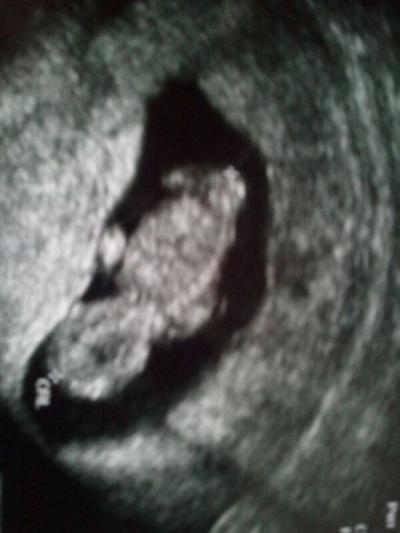

Hey MÄdels, mein Krümel hat mir gestern einen riesen Schreck eingejagt. Ich hatte plötzlich Blutungen, helles frisches Blut. Hab eine Panikattacke mit Heulkrämpfen bekommen (alles kam wieder hoch, bei meiner FG hat es auch so angefangen). Mein Mann fing plötzlich auch an zu heulen, weil er mich nicht beruhigen konnte. Er hat dann im KH angerufen und wir sind sofort hingefahren. Erstmal habe ich was zur Beruhigung bekommen und dann durfte ich Krümel sehen. Das Herz schlägt und er hat getanzt wie ein Weltmeister. Die Ärtzin meinte, dass meine Gebärmutter gerade einen Wachstumsschub hat und vllt am Muttermund gerieben hat, was die Blutung verursacht hat. Musste heute morgen nochmal zur FÄ, die ebenfalls Entwarnung gab, heute morgen hat er geschlafen. Er ist heute 4,3 cm und ich bin 11+1. Bin super happy... Allerdings habe ich jetzt wieder Angst, nachdem ich Montag nach meinem Vorsorgetermin eigentlich super entspannt war. Immer mal was neues :-/ jetzt hoffe ich, dass ich verschont bleibe und eine entspannte SS habe. Sorry ist etwas lang geworden. Anbei ein Foto, wer gucken mag :-)

Bild zu war gestern im KH - Forum für Juli - Mamis